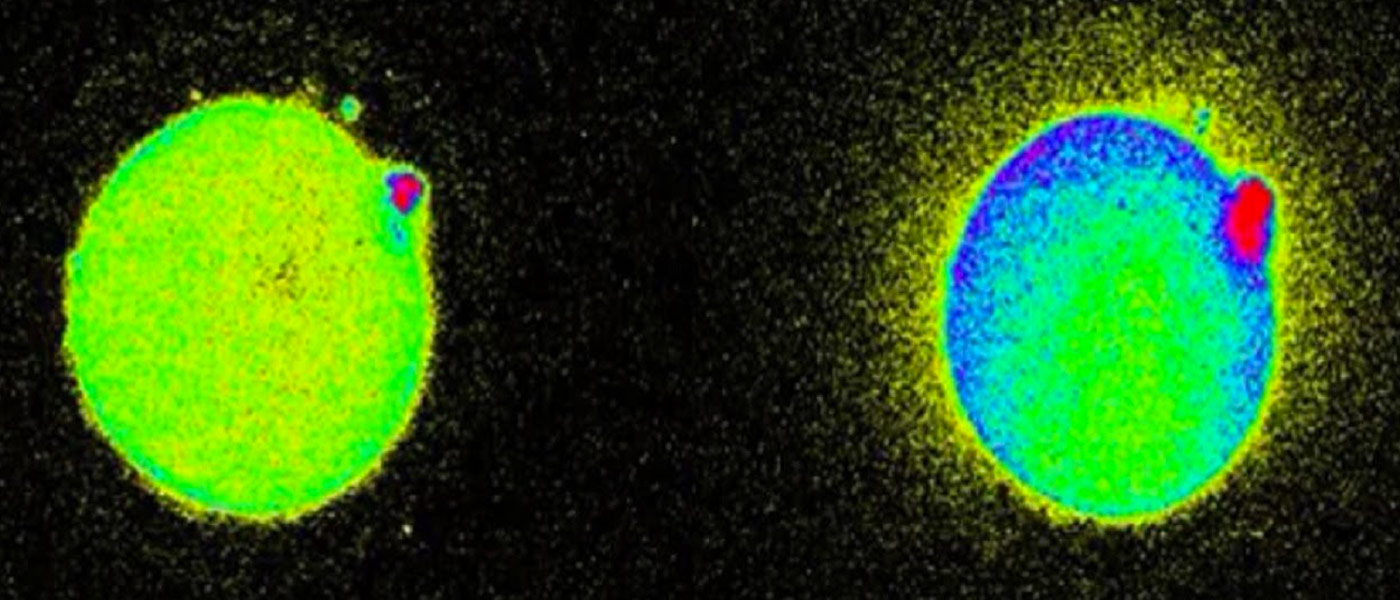

The egg cells apparently flash when pierced by sperm, as this triggers calcium levels to rise inside the egg, and prompts the release of zinc. The zinc then binds to molecules that emit a fluorescence which camera microscopes can pick up.

The zinc sparks continue like a symphony for about two hours from conception. “As the zinc shoots out, it binds to small molecules which emit a fluorescence, which can be picked up by camera microscopes,” states Sarah Knapton.

“We discovered the zinc spark just five years ago in the mouse, and to see the zinc radiate out in a burst from each human egg was breathtaking,” Teresa Woodruff, one of the researchers, adds.

The brighter the egg sparks in reaction to sperm enzyme, the more viable the egg.

“This is an important discovery because it may give us a non-invasive and easily visible way to assess the health of an egg and eventually an embryo before implantation,” asserts Eve Feinberg, who is also associated with the research. This would help minimize failed attempts at pregnancy and the emotional distress it causes by testing the viability of an egg before fertilization.